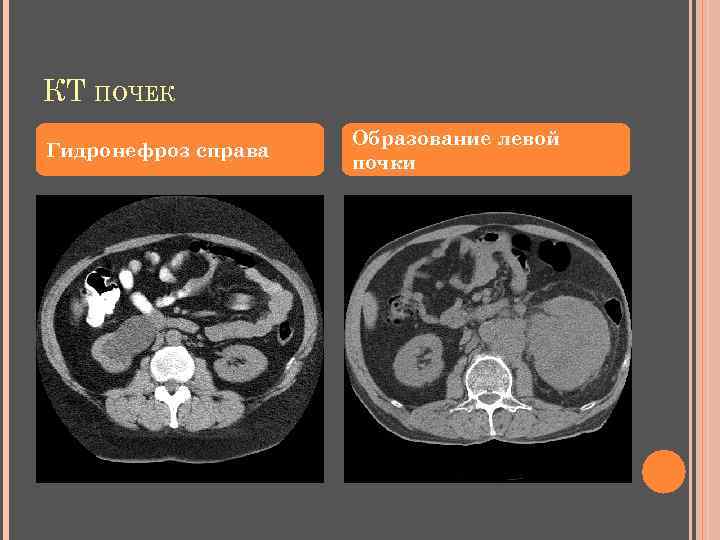

КТ ПОЧЕК Гидронефроз справа Образование левой почки